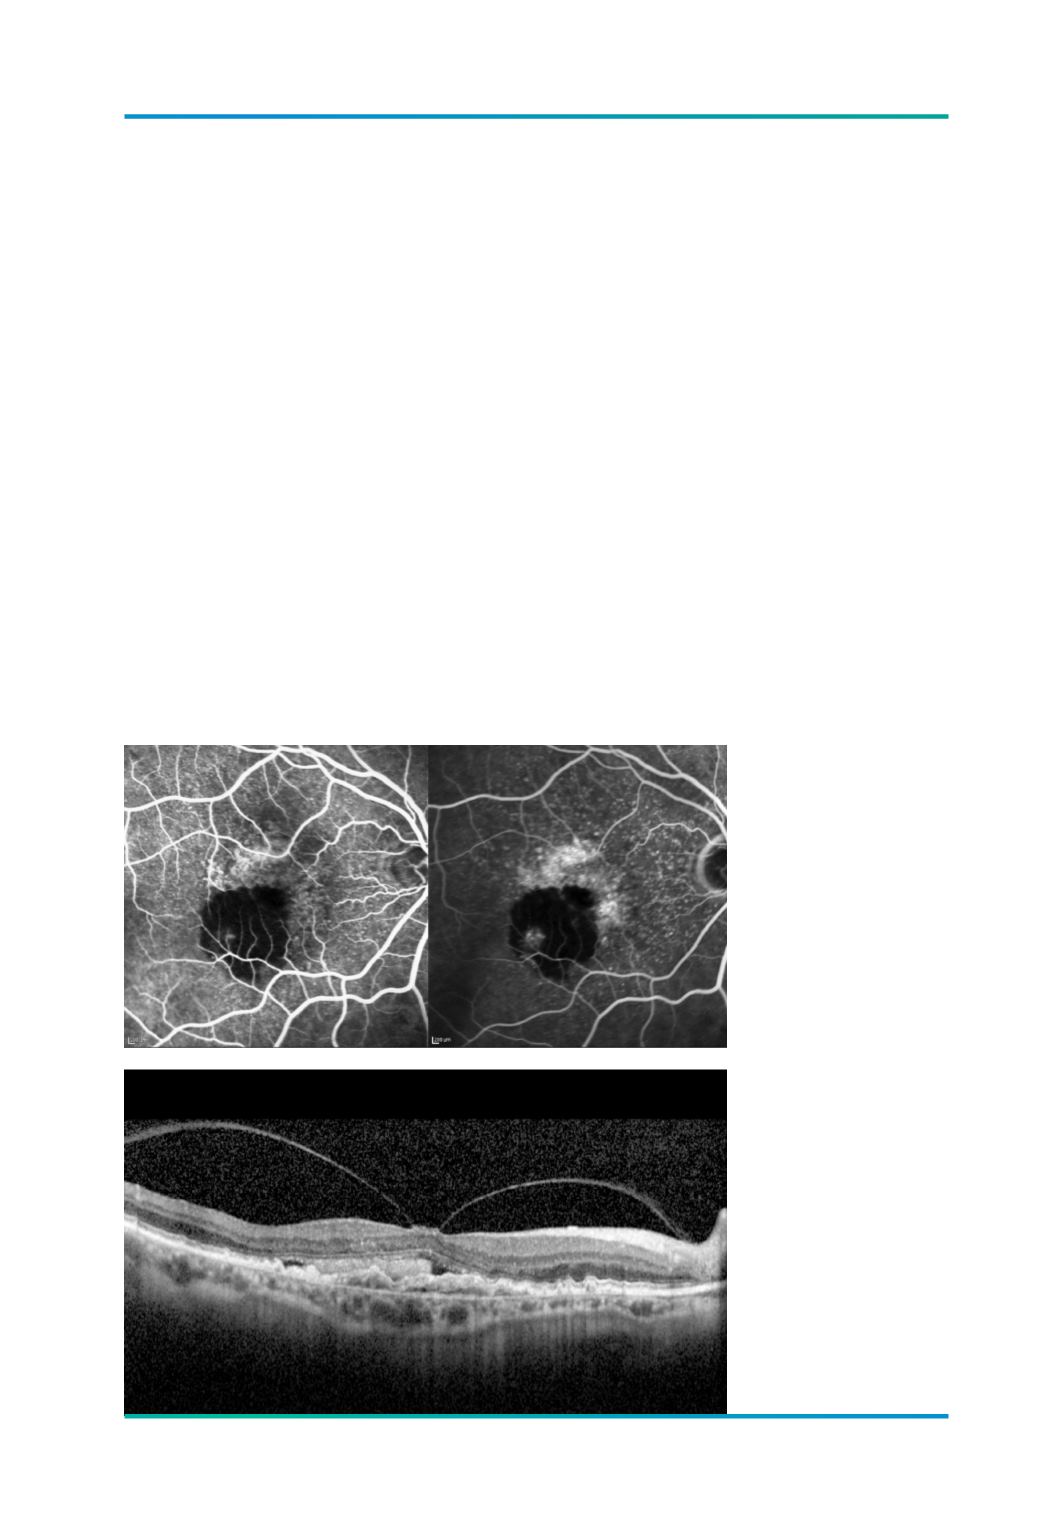

Figura 3.

Lesão de NVC

subfoveal, oculta tipo 1,

associada a TVM, antes

do inicio do tratamento

anti-VEGF.